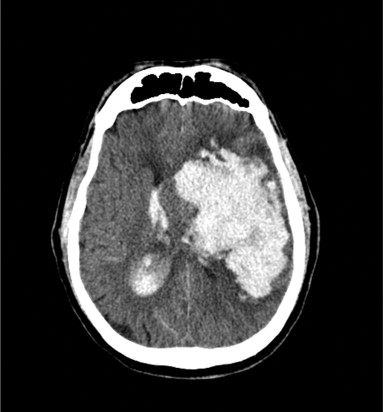

La hemorragia intracraneal es una forma de apoplejía. Para diferenciar el diagnóstico con la apoplejía isquémica se requieren estudios de imagen encefálica.

La tomografía computarizada de la cabeza es muy sensible y específica para la hemorragia intracraneal y para determinar la ubicación del sangrado.

La hemorragia intracraneal suele descubrirse al realizar una tomografía computarizada encefálica durante la valoración inmediata de una enfermedad cerebrovascular.

Alguna veces el sangrado es escaso y otras se forma un gran coágulo que comprime al tejido adyacente, provocando la herniación del cerebro y la muerte.

La sangre puede penetrar en el sistema ventricular, lo que aumenta considerablemente la morbilidad y puede provocar hidrocefalia.